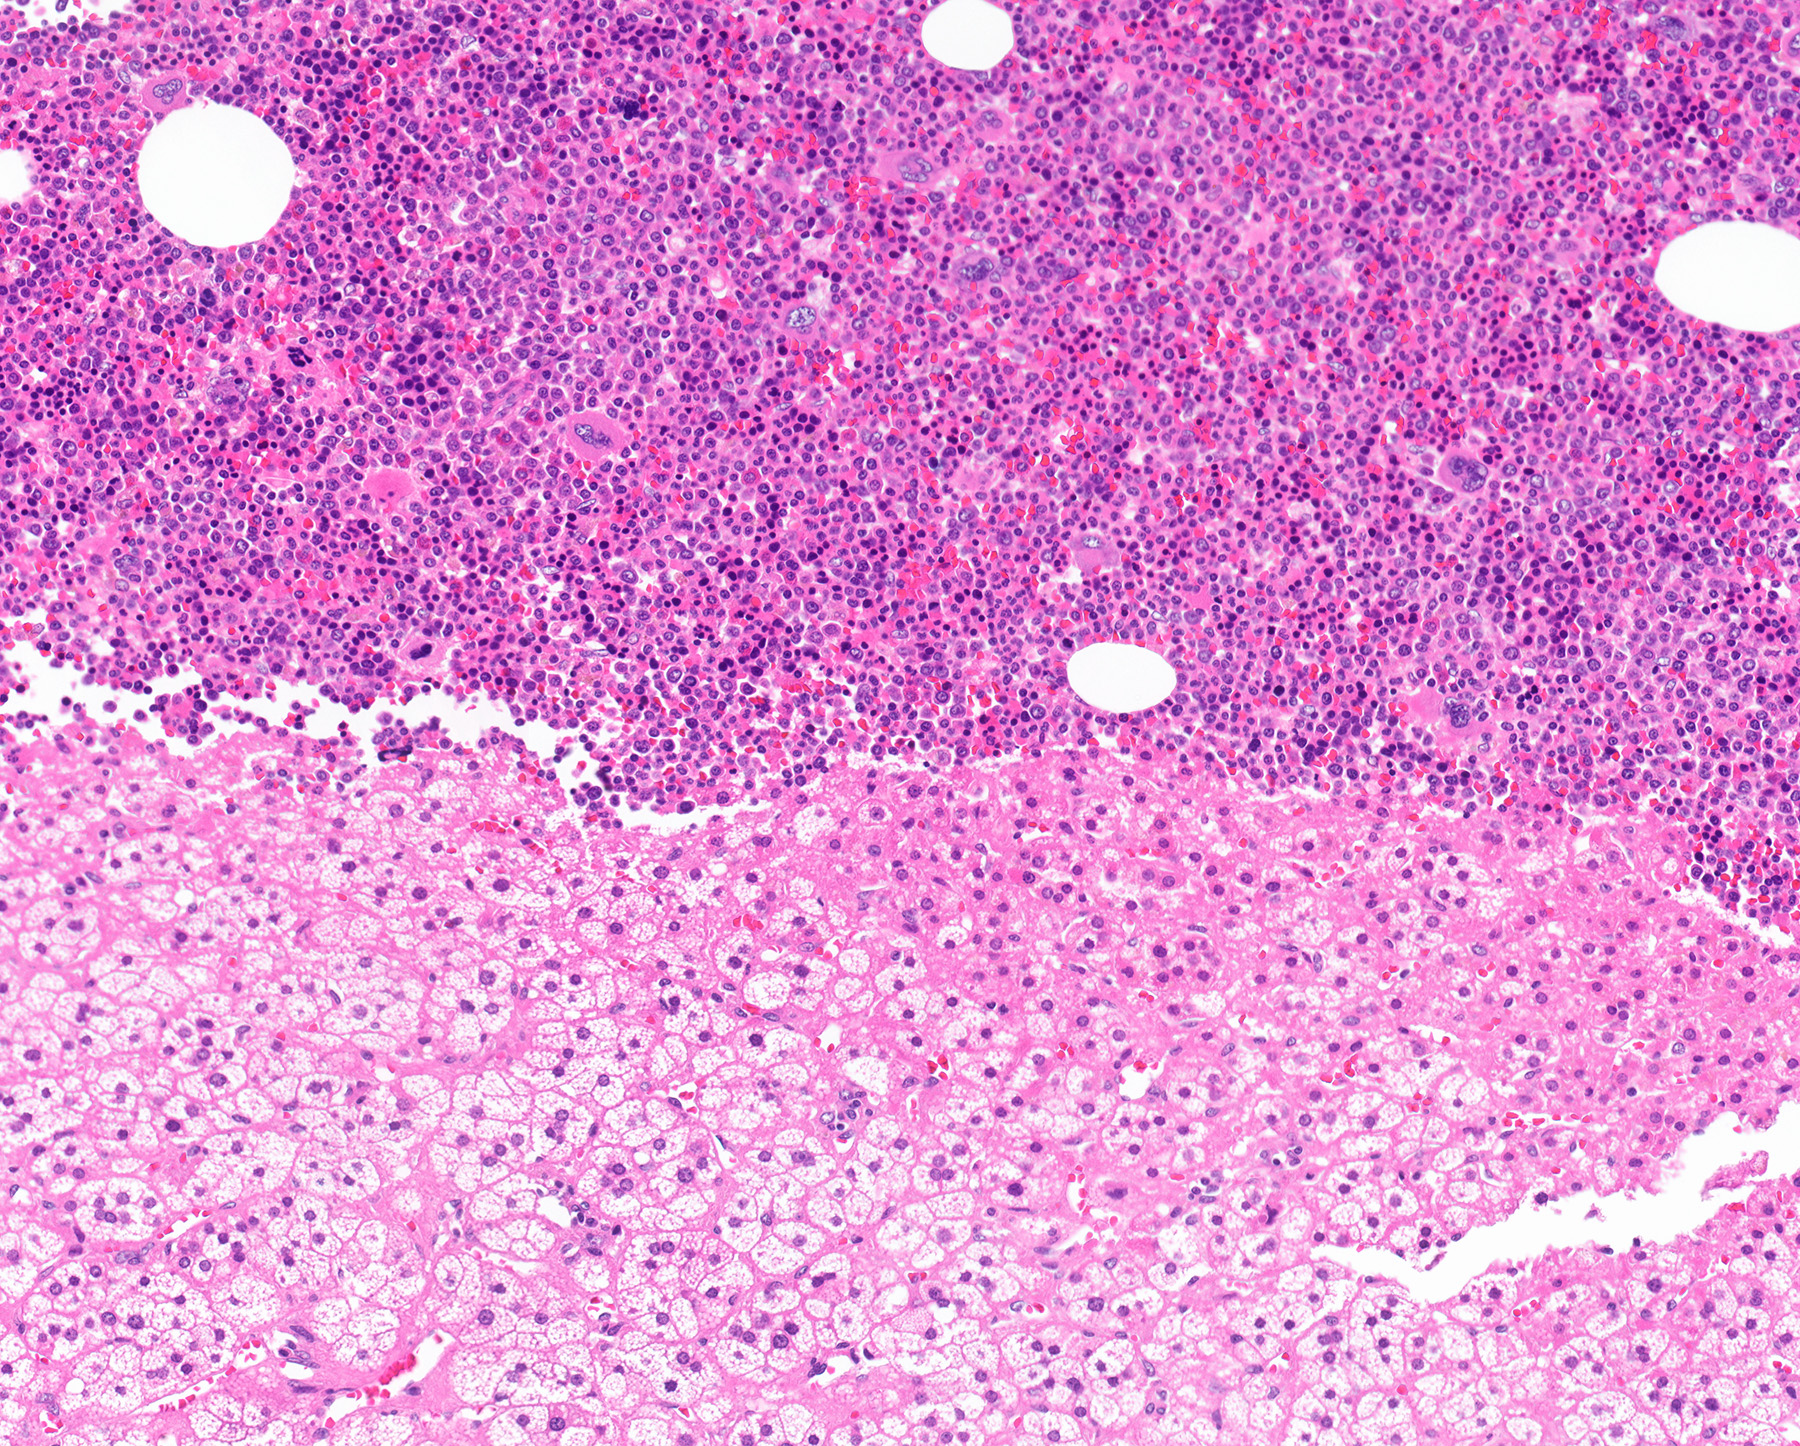

- Mixture of mature adipocytes and extramedullary trilineage hematopoietic cells with full maturation (similar to a hypercellular bone marrow) but often with a markedly increased number of megakaryocytes (Am J Surg Pathol 2006;30:838)

Microscopic (histologic) images

Contributed by Debra L. Zynger, M.D., Anil Parwani, M.D., Ph.D., O. Hans Iwenofu, M.D., Ph.D. and @ThatGlassTho on Twitter